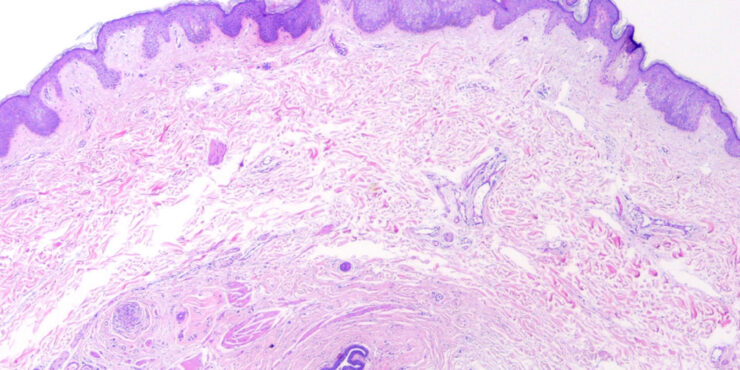

Read MoreAcanthosis nigricans =داء الشواك الأسود Acanthosis Nigricans Acanthosis nigricans can be seen in multiple clinical settings: malignancy associated, benign, inherited, obesity associated, syndromic, drug induced, and mixed (. The malignant type differs from the benign types by showing more extensive and more pronounced lesions, by its progressiveness, and by its onset usually after […]